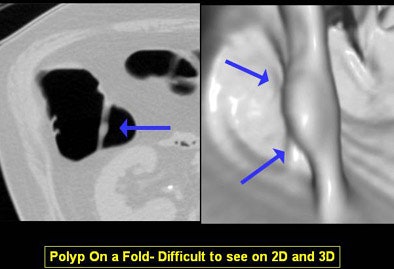

"You can differentiate folds from polyp and easily detect polyps on folds," she said. "And as shown in the Pickhardt study, you can achieve really high levels of sensitivity and specificity."

The primary 3D reader can also deviate from the flight path at any time to evaluate suspected lesions, and software can track which areas of the mucosa have been examined, Yee said. 3D can demonstrate complex, bulbous, or merging folds better than 2D.

The disadvantages include generally longer interpretation times with 3D, in addition to the time needed to process image data before it can be read. Some pitfalls are also unique to the 3D visualization process -- which can result in missed lesions or false-positive renderings of data, she said.